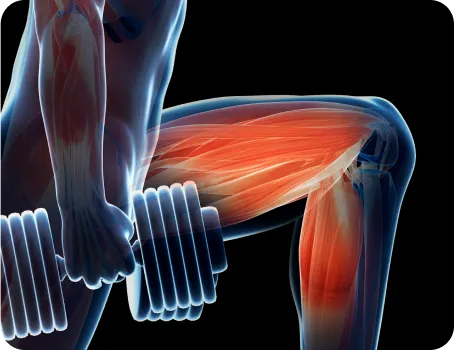

당당 도수치료는 겉과 속을 같이 치료합니다.

뼈뿐만 아니라 근육의 불균형까지 함께 보고,

재발 방지를 위해 본인도 몰랐던 보행 패턴까지 바꿉니다.

척추측만증 집중 도수치료

체형과 해부학에 대한 전문적인 지식을 바탕으로

숨은 불균형까지 교정하며, 전문 슈로스

운동요법으로 척추측만증을 바로 잡습니다.